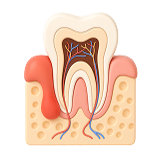

Установка имплантов вместо всех зубов предотвращает атрофию челюстной кости. Имплантат выполняет роль зубного корня и передает на челюстную кость жевательную нагрузку, аналогичную той, которую она испытывает при наличии собственных зубов. Не заметит разницы и сам пациент.

- Физиологичность

Установка условно-съемного протеза на имплантатах намного более физиологична, чем использование съемного протеза. Т.к. жевательная нагрузка на челюсть не отсутствует полностью, скорость атрофии снижается.